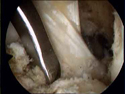

χόνδρο και τους μηνίσκους. Η αποκατάσταση των ρήξεων αυτών γίνεται

με τη χρήση των κάτωθι μοσχευμάτων:

1. Τμήμα του επιγονατιδικού τένοντα

2. Τενόντιο μόσχευμα (Hamstrings)

Αυτά τα μοσχέυματα είναι αδύνατα για την αποκατάσταση του οπισθίου

χιαστού και γιαυτό προτιμάται

3. Κατεργασμένο μόσχευμα προερχόμενο από δωρητή και ειδικά

ο αχίλλειος τένοντας

Η χρήση αυτού του μόσχευματος μας πρόσφέρει ένα πολύ ισυρό μόσχευμα

που επιτρέπει την αποκατάσταση και των δύο μοίρων του φυσιολογικού

οπισθίου χιαστού συνδέσμου. Έτσι περισσεύει το τενόντιο μόσχευμα

(Hamstrings) και μπορεί να χρησιμοποιηθεί για την αποκατάσταση

της βλάβης της οπίσθιας έξω γωνίας.